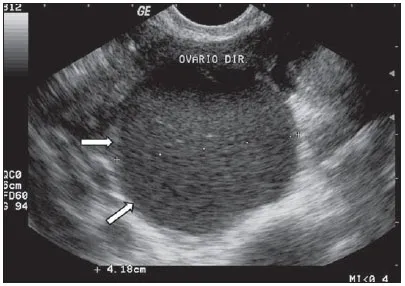

Cisto ovariano funcional em exame de ultrassom Cisto ovariano hemorrágico durante videolaparosopia